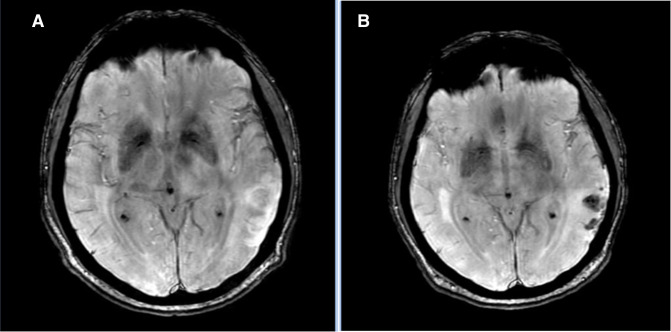

Background: The optimal time to commence anticoagulation in patients with atrial fibrillation (AF) after ischaemic stroke or transient ischaemic attack (TIA) is unclear, with guidelines differing in recommendations. A limitation of previous studies is the focus on clinically overt stroke, rather than radiologically obvious diffusion-weighted imaging ischaemic lesions. We aimed to quantify silent ischaemic lesions and haemorrhages on MRI at 1 month in patients commenced on early (<4 days) vs late (≥4 days) anticoagulation. We hypothesised that there would be fewer ischaemic lesions and more haemorrhages in the early anticoagulant group at 1-month MRI.

Methods: A prospective multicentre, observational cohort study was performed at 11 Australian stroke centres. Clinical and MRI data were collected at baseline and follow-up, with blinded imaging assessment performed by two authors. Timing of commencement of anticoagulation was at the discretion of the treating stroke physician.

Results: We recruited 276 patients of whom 208 met the eligibility criteria. The average age was 74.2 years (SD±10.63), and 79 (38%) patients were female. Median National Institute of Health Stroke Scale score was 5 (IQR 1-12). Median baseline ischaemic lesion volume was 5 mL (IQR 2-17). There were a greater number of new ischaemic lesions on follow-up MRI in patients commenced on anticoagulation ≥4 days after index event (17% vs 8%, p=0.04), but no difference in haemorrhage rates (22% vs 32%, p=0.10). Baseline ischaemic lesion volume of ≤5 mL was less likely to have a new haemorrhage at 1 month (p=0.02). There was no difference in haemorrhage rates in patients with an initial ischaemic lesion volume of >5 mL, regardless of anticoagulation timing.

Conclusion: Commencing anticoagulation <4 days after stroke or TIA is associated with fewer ischaemic lesions at 1 month in AF patients. There is no increased rate of haemorrhage with early anticoagulation. These results suggest that early anticoagulation after mild-to-moderate acute ischaemic stroke associated with AF might be safe, but randomised controlled studies are needed to inform clinical practice.